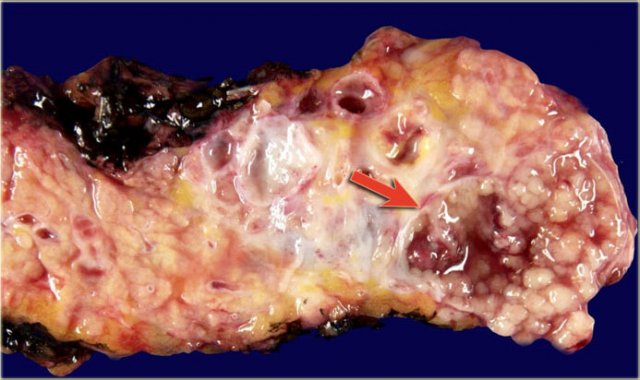

Macroscopic specimen of a IPMN showing mucinous tumor, with extensive mucin producing papilary neoplasm (arrow).

The pathology specimen shows multiple microcysts, which gives the tumor a lobulated appearance.

The pathology specimen shows a cystic tumor with multiple small cysts and a central scar.

There are no calcifications.